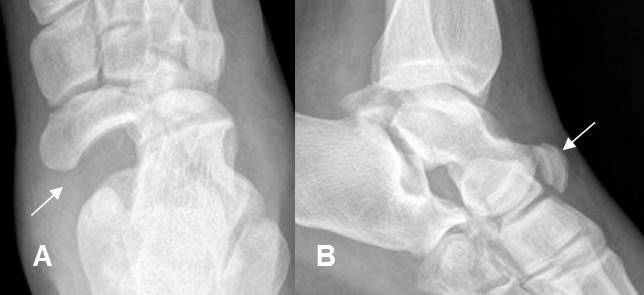

Fig 183. Fractura de Chopart.

A: Rx AP y B: Rx lateral. Luxo fractura de la articulación taloescafoidea.